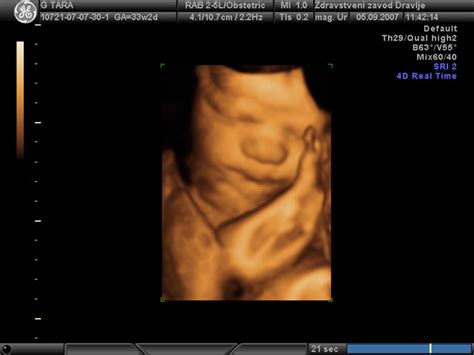

Ultrazvočne preiskave v nosečnosti izvajamo v sodelovanju s Porodnišnico Ljubljana. Prva ultrazvočna preiskava se opravi ob prvem pregledu, druga pa okrog 20. tedna nosečnosti. Druga ultrazvočna preiskava vključuje morfologijo ploda in oceno plodove rasti. Vsem nosečnicam svetujemo tudi ultrazvočni pregled zgodnje morfologije ploda z merjenjem nuhalne svetline med 11. in 14. tednom nosečnosti. Za nosečnice, stare 35 in 36 let v času pričakovanega dneva poroda, je na voljo presejalni test, ki je lahko merjenje nuhalne svetline z dvojnim testom (NS + DT) ali četverni test (ČT). Po 37. letu starosti v času pričakovanega dneva poroda pa nosečnica prejme pravico do diagnostične preiskave, kot sta biopsija horionskih resic (BHR) ali amniocenteza (AC). Sledimo tudi najnovejšim priporočilom za uporabo IgG anti D v nosečnosti. Zaščito prejme vsaka Rh-D-negativna nosečnica v 28. tednu nosečnosti, če je ICT negativen in ima Rh-D pozitiven plod. Zaščita je namenjena tudi vsaki Rh-D-negativni nosečnici, ki v nosečnosti krvavi ali ji je bil opravljen intrauterini poseg (biopsija horionskih resic, amniocenteza, placentocenteza, kordocenteza, feticid, redukcija plodov pri večplodni nosečnosti), ter vsaki Rh-D-negativni ženski po umetni ali spontani prekinitvi nosečnosti ali po zunajmaternični nosečnosti.